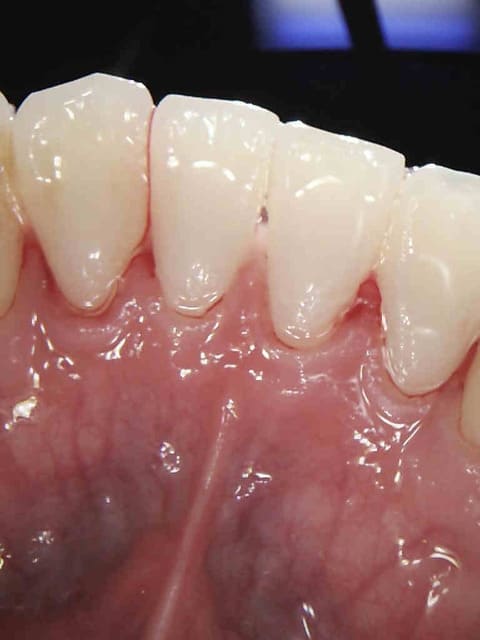

Douleur froid secteur 4. Bilan radio ( coté 6 radios, fuck le pano pas indiqué en plus source d'emmerdes-))))) détartrage.

Ordonnance méridol souple elmex vert.

1 zhor8f - Eugenol

2 efevs3 - Eugenol

3 oiohdr - Eugenol